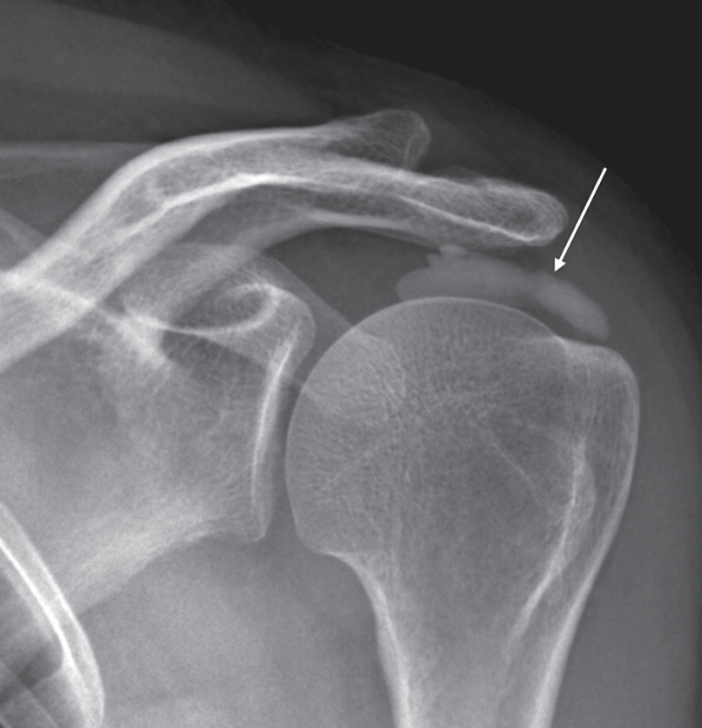

특히 봄철에는 무리한 어깨 운동으로 인해 질환 발생 가능성을 높인다. 그중 하나가 무리한 운동과 과도한 사용으로 인해 나타나는 ‘석회성건염’이다. 석회성건염은 관절에 붙어있는 힘줄 조직에 칼슘 퇴적물인 석회가 쌓여 돌처럼 굳어지는 질환으로 힘줄이 존재하는 모든 부위에 발생할 수 있지만 주로 어깨에서 발생 가능성이 높다.

주요 특징으로는 초기에는 별다른 증상을 보이지 않다가 석회가 체내로 흡수되는 과정에서 무언가로 찌르는 듯한 날카로운 통증이 발생하게 되면서 팔을 들어올리기 어려워지게 된다.

증상이 심하지 않은 석회성건염 초기에는 통증을 완화하기 위한 약물치료, 주사치료와 기능 개선을 위한 물리치료, 그리고 석회질을 분해하고 조직을 회복하는 치료인 체외충격파와 같은 치료를 고려해볼 수 있다.

하지만 석회 사이즈가 너무 크고 일상이 어려울 정도로 증상이 심한 경우에는 석회를 제거하는 수술이 필요할 수 있다. 정밀 검사 결과 석회 제거가 필요하다고 판단되는 경우에는 관절내시경을 이용한 석회제거술을 고려해볼 수 있다.